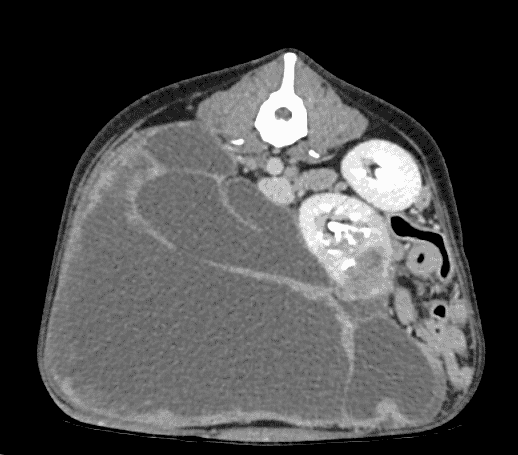

“We performed a contrast-enhanced CT scan with an iodine-based contrast to help highlight the areas of the body we needed to examine and the results were startling.

“The mass was enormous. It almost completely filled the abdomen.”

The dramatic CT images showed that the mass had originated in the right kidney, which had been displaced into the left side of the abdomen, and also compressed the rest of Penny’s internal organs. There was no evidence of metastatic disease.